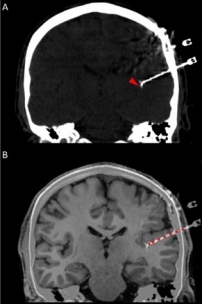

In addition to the very valuable iEEG recordings from the clinical macroelectrodes, our iEEG recordings also include signals recorded with microelectrodes. The additional microelectrodes have a diameter of about 40 μm (smaller than the hair) and spread out of the tip of the clinical intracranial electrode. They are added solely for research purposes and, because of their small size, they can record the electrophysiological firing activity generated by nearby individual neurons. We analyze this data by using algorithms which classify the different waveforms recorded by a single microwire into action potentials generated by different neurons. We also use population decoding methods to extract the information associated by the neurons (e.g. “concept” neurons which preferably fire in response to specific images of the same individual). To localize the site of the macro- and micro-electrodes with high spatial resolution, we combine post-implantation CT scans with pre-implantation neuroimaging scans from the 7-Tesla MRI, available at the University of Magdeburg.

4. © Carlson et al., 2018. Reproduced according to the terms of Creative Commons Attribution License. Carlson, April A., Ueli Rutishauser, and Adam N. Mamelak. 2018. “Safety and Utility of Hybrid Depth Electrodes for Seizure Localization and Single-Unit Neuronal Recording.” Stereotactic and Functional Neurosurgery 96 (5): 311–19. https://doi.org/10.1159/000493548.